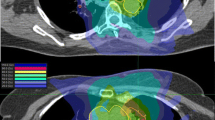

The initial literature search was also based on studies identified by Kang et al. [3], and extended to a wide range of literature offered by citation analysis and manual as well as electronic reference chaining. Lung tumors located within 2 cm around the proximal tracheobronchial tree, or at a maximum distance of 1 cm from the heart and pericardium, and the esophagus were considered as central. To synthesize the literature data in the form of a comprehensive review, an approach incorporating qualitative research synthesis methodology was used. The key process involved in this review is illustrated in Table 1.

Individual data of 115 (7 %) patients (4.6 % of all patients treated in studies including central lesions) were extracted, reviewed, and characterized. Tracheobronchial toxicity was the most frequently reported (6.7 %). Other endpoints, including cardiac toxicity, respiratory failure, fatal hemoptysis, and esophageal toxicity ≥ G3, were equally reported, with rates of 2.8 %, 2.2 %, 2.3 %, 2.4 %, and 2.4 %, respectively. Overall, specific late toxicity occurred with a median total dose of 50 Gy (range 40–54 Gy) and a median biologically effective dose with α/β = 3 Gy (BED3) of 216 Gy3 (210–277 Gy3) in the hottest/shortest regimes compared with a median total dose of 45 Gy (range 30–50 Gy) and a median BED3 of 176 Gy3 (90–237 Gy3) in the coldest/longest regimes. A summary of toxicity data is shown in Table 2.